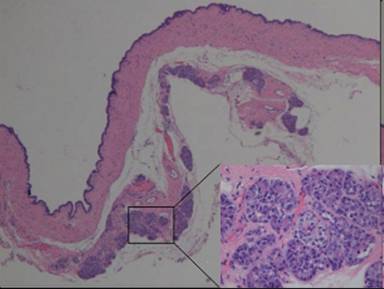

The lining cells had eosinophilic to basophilic cytoplasm without nuclear atypia, mitosis, or mucinous differentiation. No ovarian-like stroma was seen. Occasional small clusters of residual pancreatic elements including islet cells and acinar glands were also seen in the cystic wall (Figure 5).

Figure 5. Focal pancreatic islet cells and acinar glands were also seen in the cystic wall. |

The cystic lining cells were focally reactive to CK7 and Trypsin (Figure 6a) but negative for calretinin, WT1, PAX8, CD31, and CK20. The luminal border of the epithelium was also reactive to EMA. Histochemical staining for PAS was negative in the epithelium. The residual pancreatic islet could be highlighted by IHC stain for synaptophysin (Figure 6b). The whole picture was more like a rare acinar cell cystadenoma.